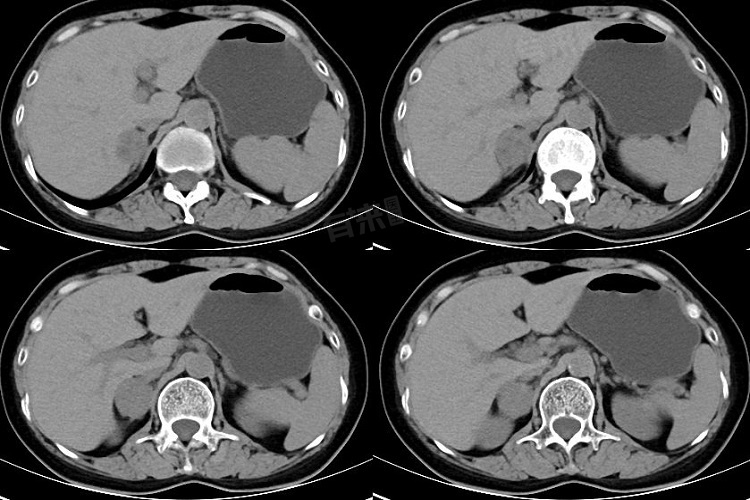

肾上腺占位是指在进行影像学检查如超声、CT、MRI等时,发现肾上腺部位存在异常的肿块或肿物。一旦发现肾上腺占位,应及时就医,进行详细的检查和评估,以确定占位的性质,并采取相应的治疗措施。

- 肾上腺皮质腺瘤:较为常见,多为良性肿瘤,可能会分泌过多的皮质醇、醛固酮等激素,引起库欣综合征,表现为满月脸、水牛背、向心性肥胖等,或原发性醛固酮增多症,表现为高血压、低血钾等。

- 嗜铬细胞瘤:可分泌大量儿茶酚胺,导致血压急剧升高、心悸、头痛、多汗等症状,发作间歇期血压可正常。

- 肾上腺转移瘤:通常由其他部位的恶性肿瘤转移而来如肺癌、乳腺癌、肾癌等。

- 肾上腺囊肿:一般为良性病变,多数无明显症状,较大的囊肿可能会压迫周围组织引起不适。